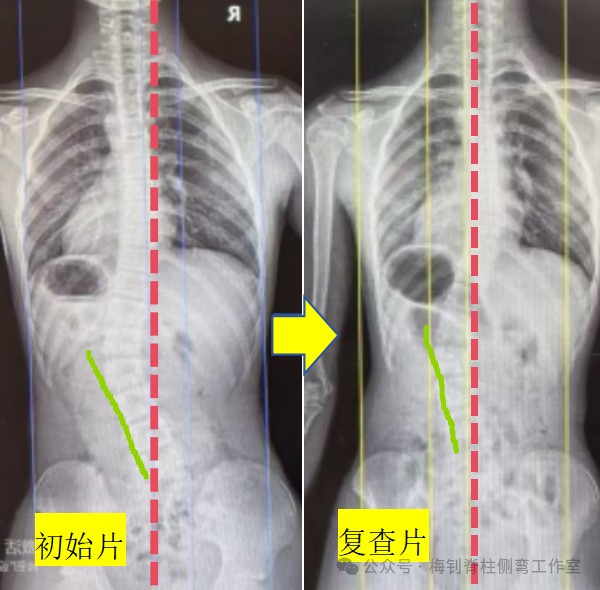

14岁女孩,生长末期,复查拍片后,被骨科医生告知,侧弯加重了,支具不合格,建议更换。家长马上比较忧虑,孩子也急哭了。家长马上把片子发给我们,当看到片子我们放心了:复查片力线明显好转,腰椎下半段明显变直,顶椎偏移程度降低,侧弯度数好转不多,但没有加重,只是医生测量的“加重”,所以,X线片复查结果整体向好。后面孩子来复查,体表的好转也印证了侧弯整体向好的结果。

为了彻底消除家长的顾虑,支具根据现状稍作调整后,再次拍片查看,结果比较理想,家长也彻底放心了。对于该骨科医生的建议,我们不做评论,或许他真的不懂吧~